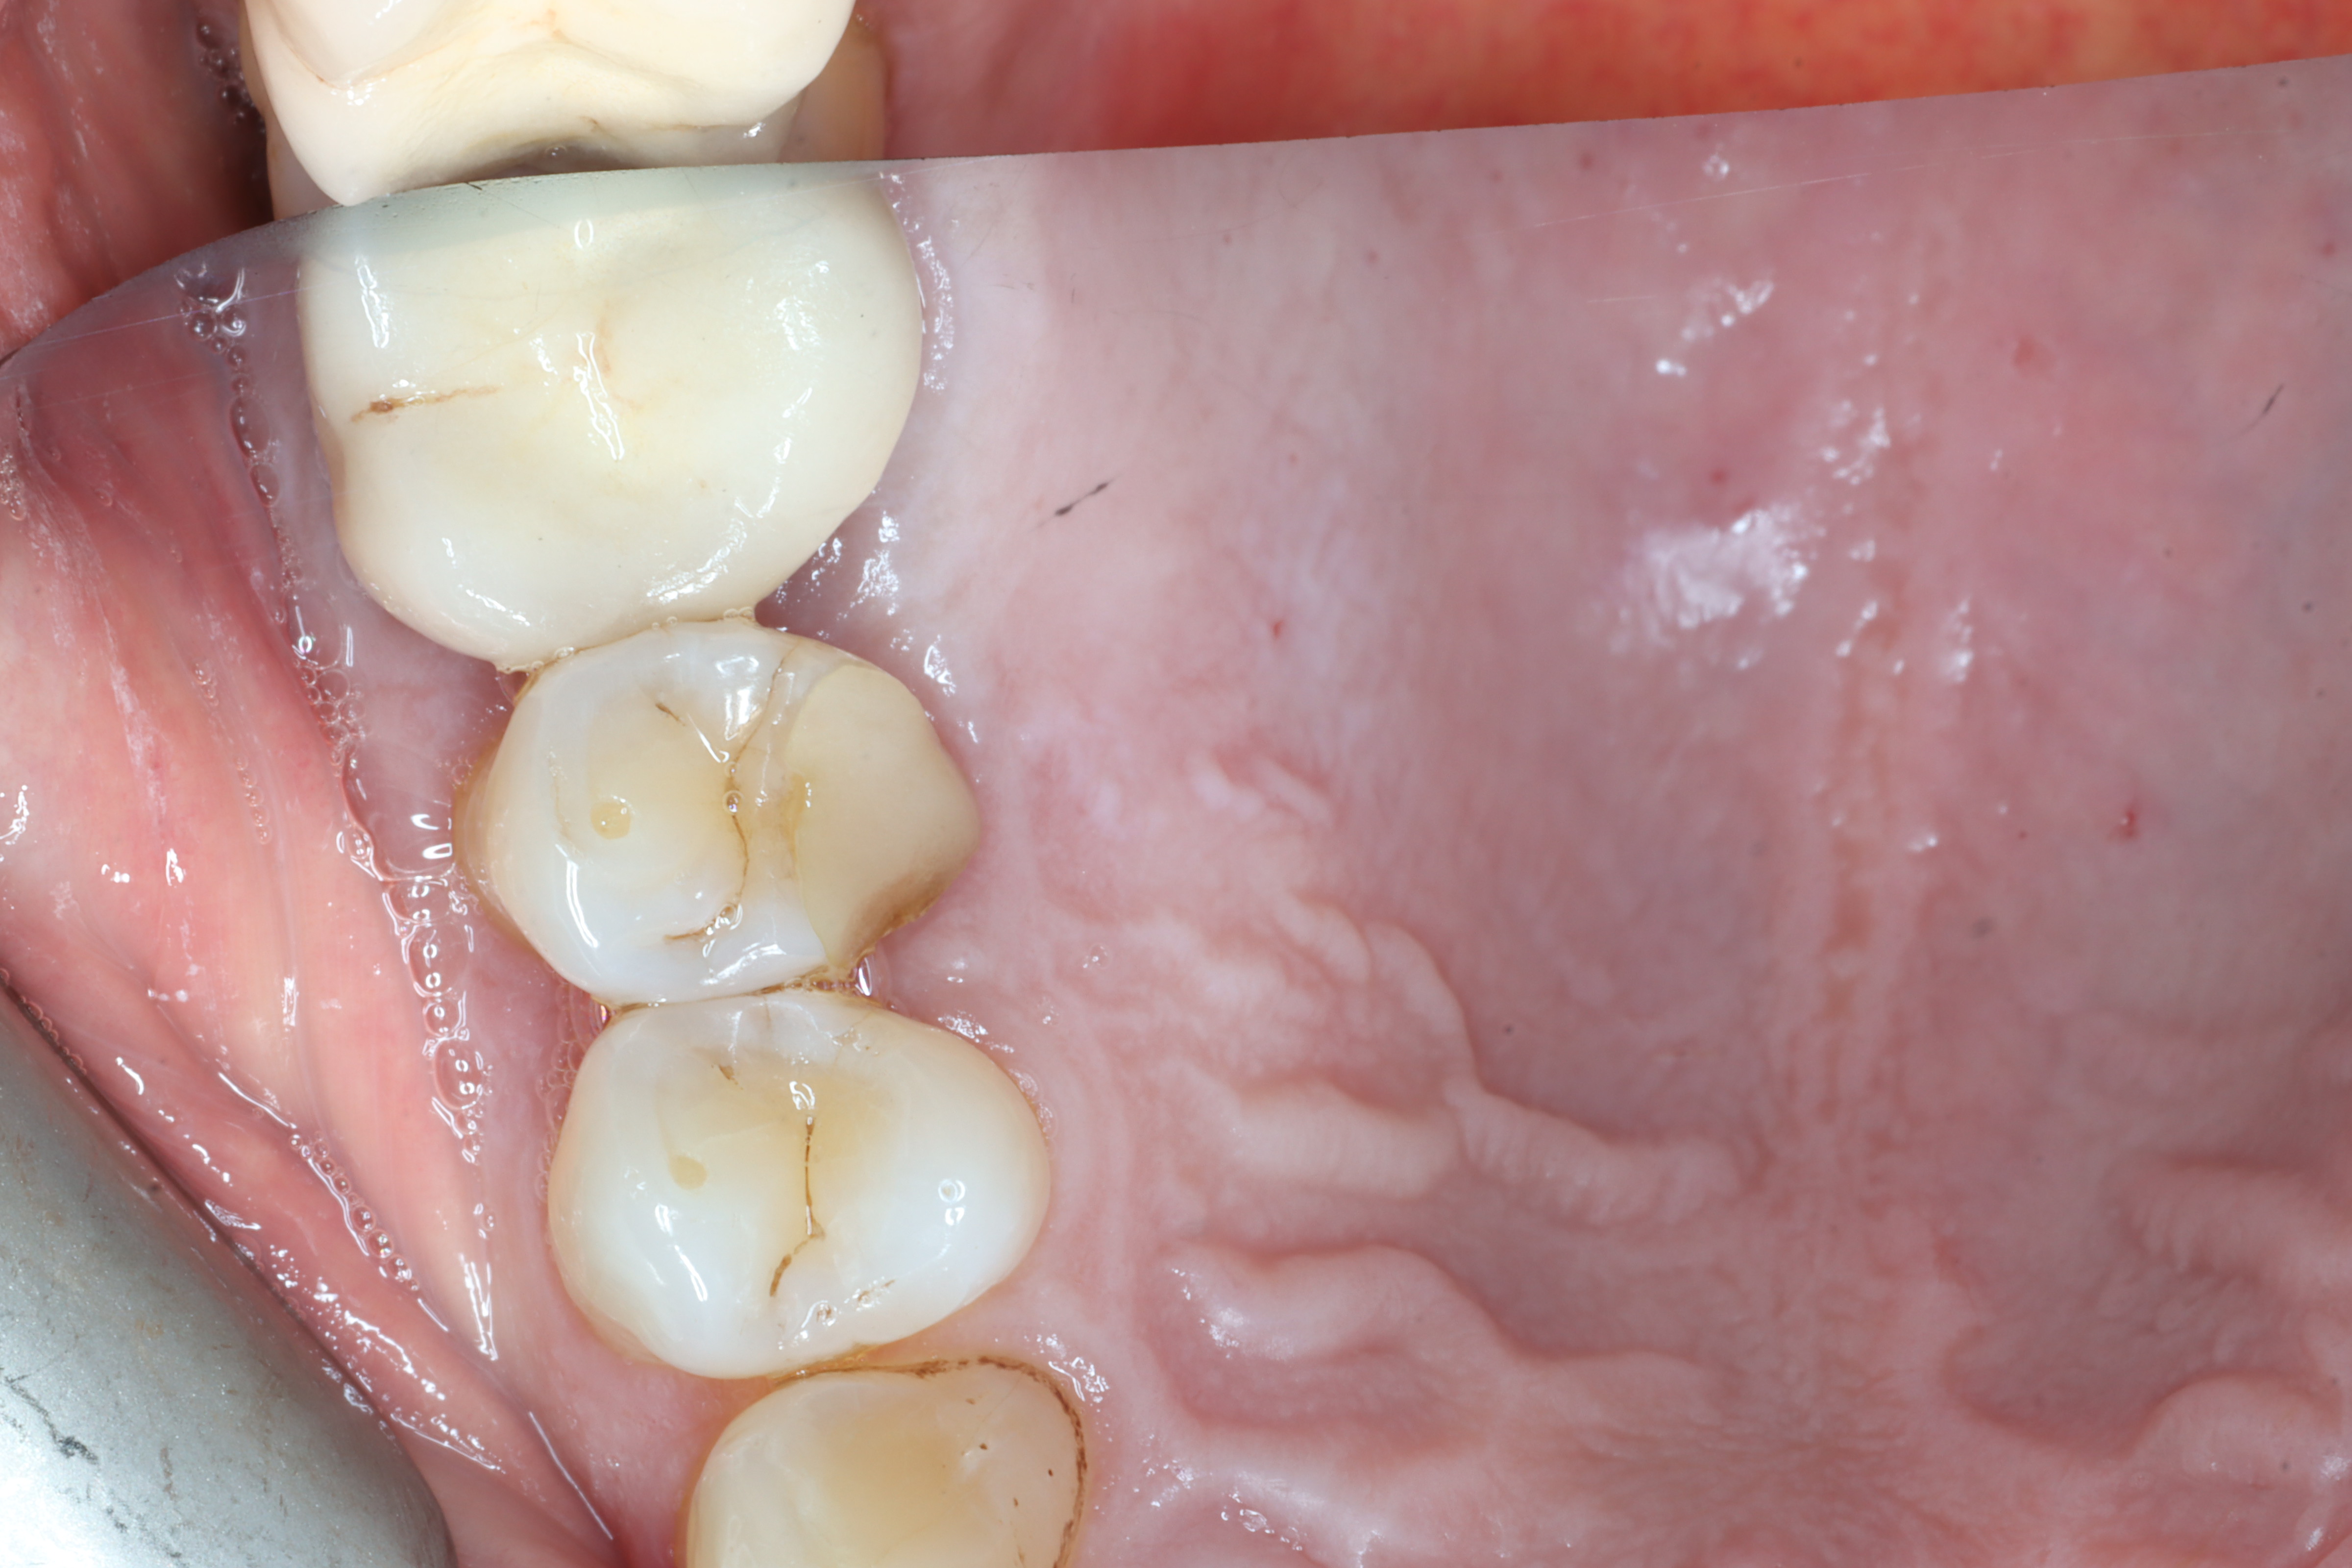

Case 6 – Periodontics

Crown lengthening Surgery on a premolar